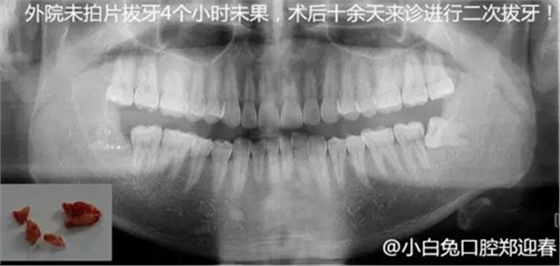

下邊也是一個(gè)斷根病例